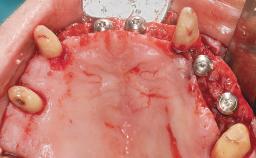

Immediate Loading of Six Implants in the Maxilla and Final Restoration with a Full-Arch CAD/CAM Zirconia FDP

A 63-year-old male patient was referred for a consultation and treatment of partial edentulism in the maxilla. The patient presented with residual anterior teeth and declined a partial removable prosthesis. He reported that the maxillary posterior teeth had been extracted due to mobility and periodontal disease two months before the consultation. The patient’s chief complaint was that his residual maxillary teeth were mobile and that he was unable to chew. The patient’s desire was a stable and comfortable fixed maxillary rehabilitation. The patient was a light smoker (fewer than 10 cigarettes/ day), and his medical history was without significant findings. He was not on any regular medication at the time of consultation. The extraoral examination revealed a normal physiognomy with a correct distribution of the facial thirds. The patient presented a low lip line, and the transition line between teeth and soft tissues was not exposed during a forced smile.

Bone Augmentation Horizontal|Simultaneous

Augmentation Materials Xenogenous

Defining Characteristics Fully edentulous upper jaw to be rehabilitated with four or more implants

Modality 6+ implants with immediate loading